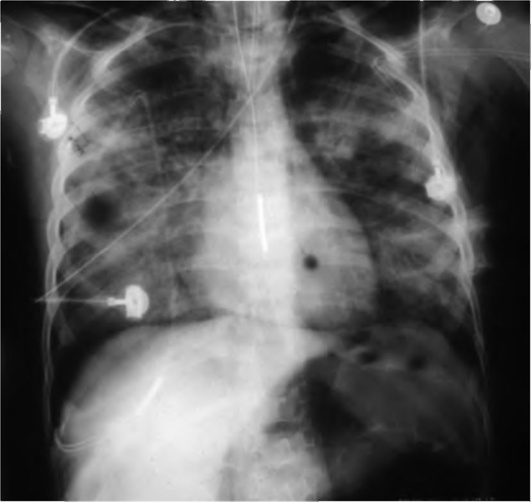

Заболевание развивается внезапно: гипертермия, одышка, выраженное беспокойство. В легких на выдохе выслушивают свистящие хрипы, активизирована работа дыхательных мышц. Работа межреберных и диафрагмальных мышц, участвующих в акте дыхания, при остром бронхиолите увеличена в среднем в 6 раз. Дыхание становится частым и поверхностным, создается впечатление, что грудная клетка эмфизематозна (рис. 3-4).

image

Рис. 3-4. Схема клинических проявлений бронхиолита

При рентгенологическом исследовании выявляют отчетливую эмфизематозность легочных полей.